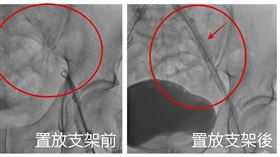

腳部冰冷竟是腳中風險截肢!醫曝3大警訊

天冷腳麻別輕忽!婦「腳中風」險截肢

腳痠麻竟是腳中風!醫:小心發黑截肢

一位90歲的謝奶奶因為左腳痠麻、腳底疼痛到醫院就診,...